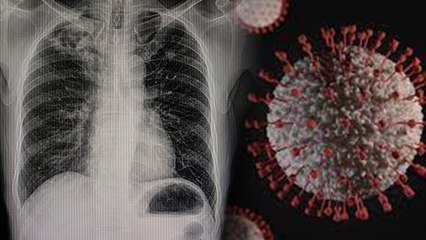

With the second wave of Corona, the number of infected in India is increasing continuously. Many new symptoms are also being seen in this wave, which are indicating that this virus is affecting not only the lungs but also other parts of the body. Health experts say that as the corona virus attack increases in the body, it is weakening the immune system and causing inflammation in other body parts. If a person has diabetes, hypertension or obesity, then corona has more effect on the body. In such a situation, it is important that after getting infected with Korana, you should pay attention to all your symptoms and do not ignore any changes happening in the body. Let us know how the corona is affecting our whole body.br br कोरोना की दूसरी लहर के साथ ही भारत में संक्रमितों की संख्या लगातार बढ़ती जा रही है. इस लहर में कई नए लक्षण भी देखे जा रहे हैं जो इस बात का संकेत दे रहे हैं कि ये वायरस ना सिर्फ फेफड़ों बल्कि शरीर अन्य हिस्सों पर भी असर डाल रहा है. हेल्थ एक्सपर्ट का कहना है कि जैसे-जैसे शरीर में कोरोना वायरस का हमला बढ़ता है, ये इम्यून सिस्टम को कमजोर करने के साथ-साथ दूसरे बॉडी पार्ट्स में सूजन पैदा कर रहा है. अगर किसी व्यक्ति को डायबिटीज, हाइपरटेंशन या मोटापे की समस्या है तो फिर कोरोना का शरीर पर असर और ज्यादा होता है. ऐसे में जरूरी है कि आप कोराना से संक्रमित होने के बाद अपने सभी लक्षणों पर ध्यान दें और शरीर में हो रहे किसी भी तरह के बदलाव को नजरअंदाज ना करें. आइए जानते हैं कि कोरोना हमारे पूरे शरीर को किस तरह प्रभावित कर रहा है.